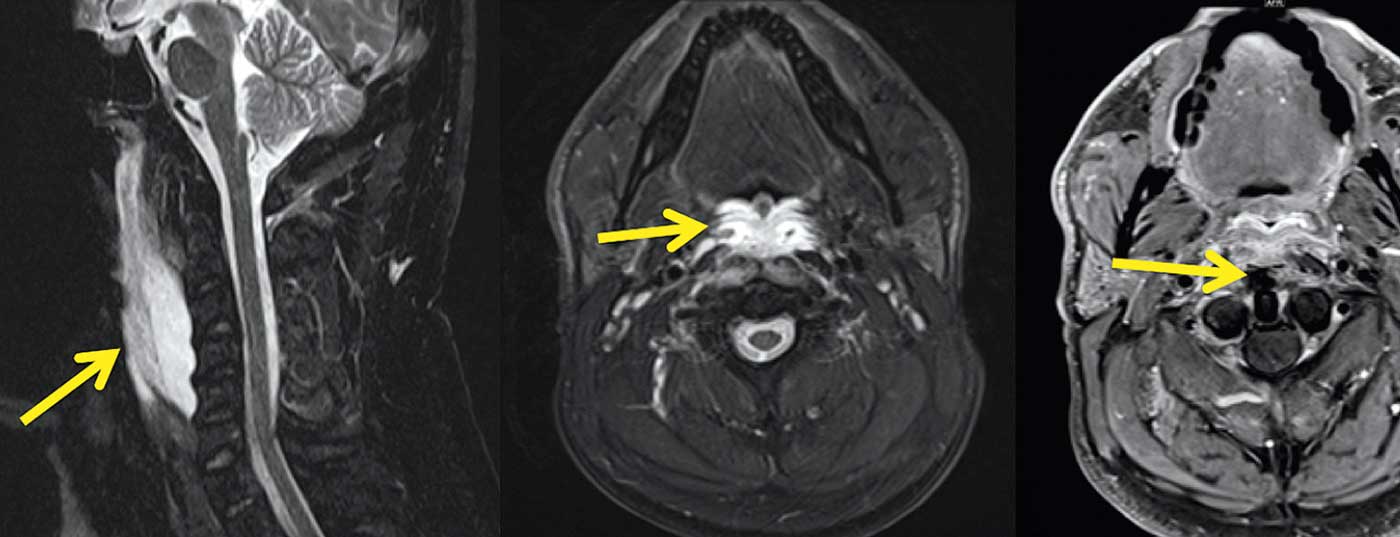

La faringo-laringoscopia non ha rivelato alcuna evidenza di infezione locale, ma i riflessi di deglutizione erano assenti alla provocazione del dolore sulla parete faringea posteriore. La successiva risonanza magnetica del collo ha dimostrato una marcata alterazione del segnale del muscolo longus colli, con una formazione iperintensa T2w a forma di fuso lungo tra il muscolo longus colli e la parete faringea posteriore (Fig. 1A) senza restrizione della diffusione e con una moderata e marginale captazione del contrasto. C’era anche un edema della parete faringea posteriore, compresa la mucosa (freccia nella Fig. 1B) e alterazioni di segnale piuttosto lievi nei tessuti molli adiacenti. Non c’erano linfadenopatie evidenti. Questi reperti tendevano a sconsigliare un ascesso retrofaringeo, che poteva essere escluso anche mediante una puntura locale (poco liquido sieroso senza evidenza di germi). Con un segnale regolare dai corpi vertebrali cervicali, era anche improbabile che la spondilodiscite fosse la causa di una raccolta retrofaringea.

In T1w e T2w, sono state trovate strutture a basso segnale nell’inserzione del tendine del muscolo longus colli al tubercolo antero dell’atlante (freccia in Fig. 1C), Questo ha portato al sospetto di una rara tendinite acuta e calcificante del muscolo longus colli, che è stata confermata nel corso dell’esame mediante una TAC del collo.

Le calcificazioni amorfe nel tendine del muscolo lungo (Fig. 1C-E) sono patognomoniche per questo quadro clinico. Dopo alcuni giorni di terapia steroidea e successiva terapia antinfiammatoria, la tendinite è chiaramente scomparsa, così come i disturbi del paziente.

La M. longus colli è composto da tre parti, pars obliqua superior, pars recta e pars obliqua inferior(Fig. 1F). Nella tendinite calcificante, tipicamente le fibre della pars obliqua superior (freccia in Fig. 1F) con attaccamento al tubercolo anterius atlantis colpito da calcificazioni tipiche che portano alla diagnosi. Nel caso mostrato, c’è un’effusione retrofaringea pronunciata, ma questa può anche essere molto più stretta e manifestarsi solo come una traccia di fluido retrofaringeo larga qualche millimetro. Comuni a tutti i casi sono le calcificazioni patognomoniche dell’attacco del tendine.